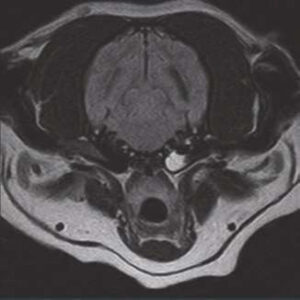

- Image Quality comparable to 1.5T MRI in the market

The PANION PRO comes with the double-pole open magnet design with a wide opening gap of 40 cm to accommodate large-sized animals on an efficient patient handling platform, the strongest gradient amplitude at 33mT/m and slew rate of 90 T/m/s, among all other open MRI systems, resulting in high spatial resolution of images in short scan time. The 6-direction patient table permits iso-centre imaging of all anatomical regions.

Clinical Images